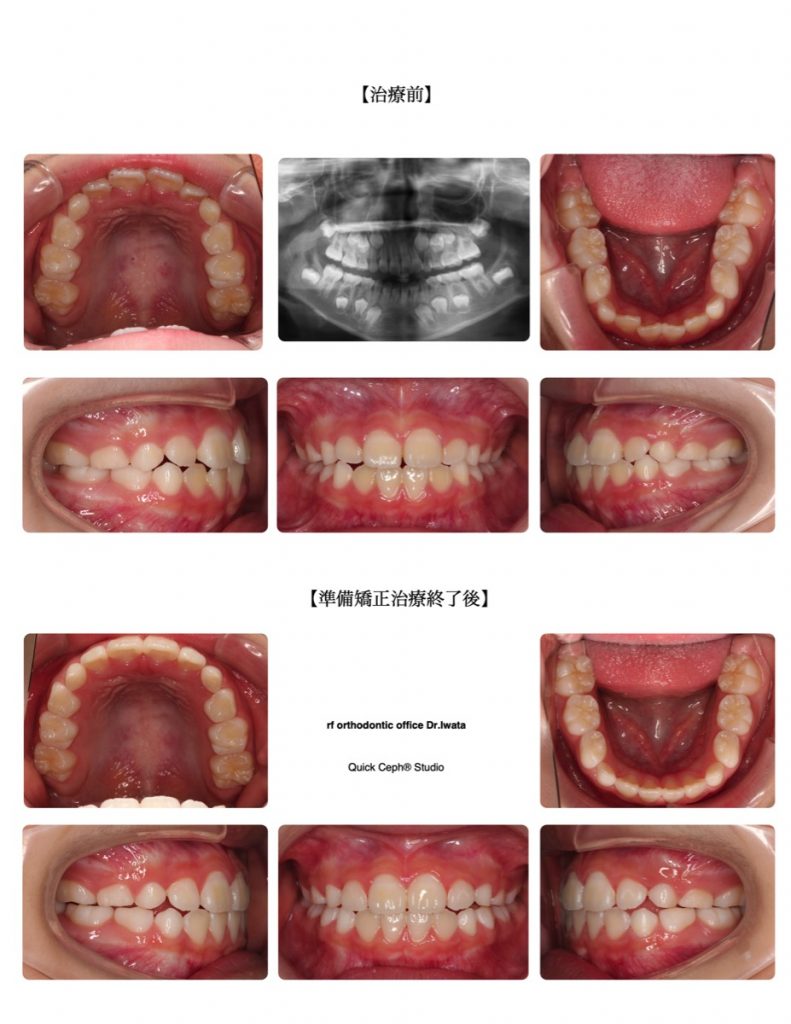

叢生症例 <上下顎前歯部の叢生に対する準備矯正治療>

【主訴】上下の前歯のデコボコが気になり始めた。今後の永久歯への生え変わりもすき間がなくて心配。歯磨きもしづらくむし歯のリスクも気になる。

【主な症状】叢生